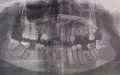

Что можно сделать в моем случае, кроме имплантов?

Комментарий №177214

• Наилучшим вариантом протезирования будет имплантация, долговечно, прочно и эстетично. В данном случае можно выбрать бюгельный протез или частично съёмный протез. Проконсультируйтесь очно со стоматологом-ортопедом.